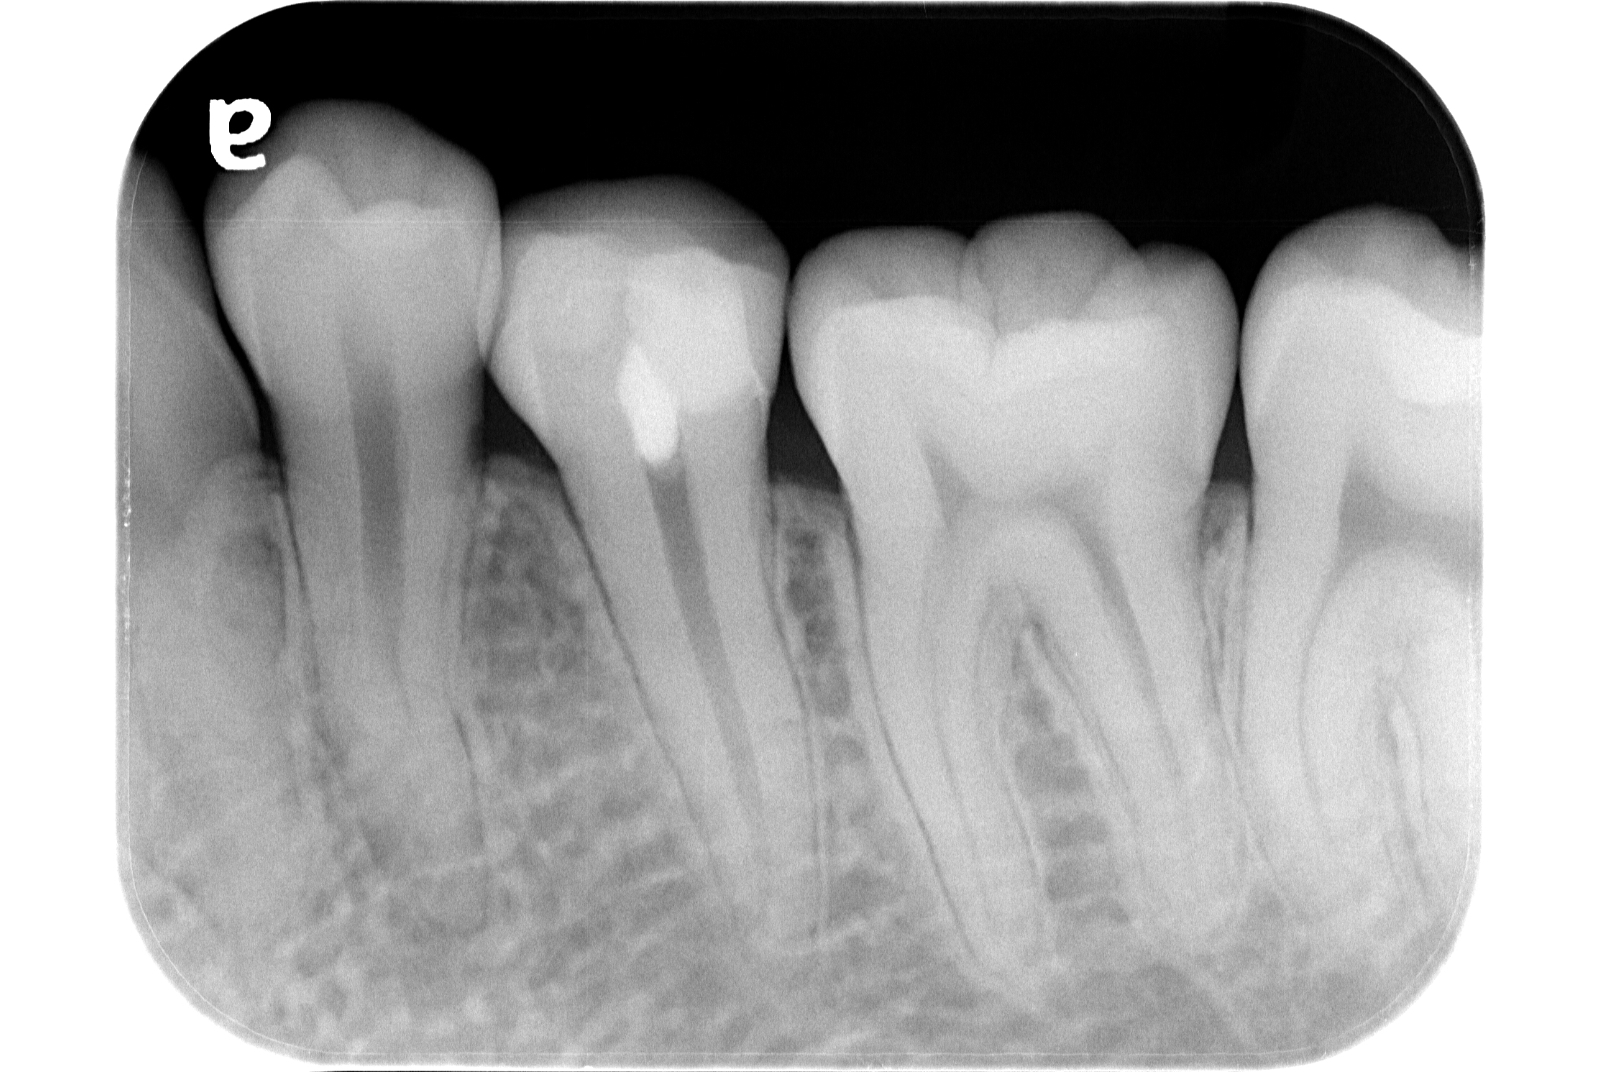

治療例 写真とレントゲン

治療前

治療後

※治療例に記載の情報はあくまでも症例に対してのものとなります。

| 費用 | 部分断断髄 44,000円(税込) |

|---|---|

| MTA 5,500円(税込) | |

| 治療期間 | 1日 |

| 治療回数 | 1回 |

| 主な副作用とリスク | 歯髄保存療法が奏功しなかった場合、根管治療へ移行します。 根管治療が必要となった場合、修復物を除去することがあります。 |